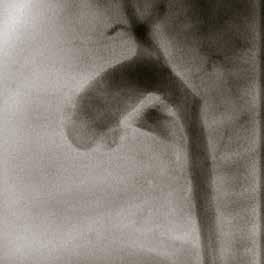

urVena is advancing coronary artery bypass grafting (CABG) with its novel PTP technology, a point-of-care therapy designed to strengthen venous tissue and dramatically improve long-term vein graft durability. Despite advances in surgical techniques and medical management, CABG's efficacy remains limited primarily due to vein graft failure and the progression of atherosclerosis in native coronary arteries. Vein graft failure is ascribed to the luminal narrowing that results from intimal hyperplasia, medial thickening, and subsequent concomitant accelerated atherosclerosis. Structurally, veins are not designed to withstand arterial pressure. Vein grafts excessively expand under arterial pressure, causing irreversible injury and progressive endothelial remodeling. Vein grafts are subject to reported degeneration and occlusion rates from 20-40% in the first year and as high as 50% at five years. SVG failure is associated with a significant increase in major adverse cardiovascular events (MACE), including death, myocardial infarction (MI), and the need for repeat revascularization.

DurVena’s PTP device addresses this challenge by applying Rose Bengal dye, a photo-initiator with a long history of medical use, to the exterior of the harvested vein. The coated vein is then exposed to LED light, which activates the dye, thereby creating additional collagen crosslinks in the extracellular matrix of the vein's adventitia. The collagen crosslinks increase tissue strength and decrease elasticity without altering the histological makeup of the vein. In extensive, published pre-clinical testing of PTP in both small and large animals, a significant increase in vein stiffness (5-fold), a comparable reduction in vein expansion, and a reduction in intimal hyperplasia (a precursor to stenosis and graft failure) have been demonstrated. In addition, Durvena has also completed a first-in-human safety study demonstrating no device-related events at 30 days, 6 months, and one year.

PTP therapy is precise and localized. Rose Bengal binds non-covalently to collagen in the extracellular matrix. Upon illumination, it forms covalent crosslinks between collagen

molecules, reinforcing the tissue. The dye penetrates only about 100µm into the adventitia, forming a stable surface band. There is no change to the histological makeup of the vein. The entire process is monitored by validated software, ensuring consistent and safe application.